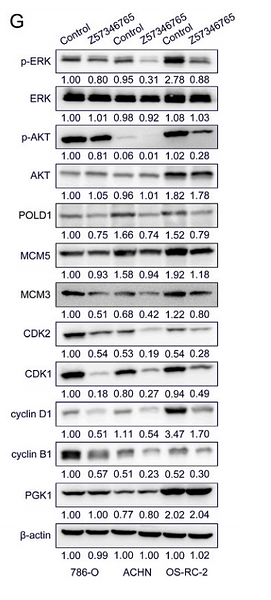

Novel inhibitors targeting the PGK1 metabolic enzyme in glycolysis exhibit effective antitumor activity against kidney renal clear cell carcinoma in vitro and in vivo

Author: Yu He, Yinheng Luo, Lan Huang, Dan Zhang, Huijin Hou, Yue Liang, Shi Deng, Peng Zhang, Shufang Liang

PMID: 38354523

期刊: European Journal Of Medicinal Chemistry

应用: WB

反应种属: Human

发表时间: 2024 Feb

-